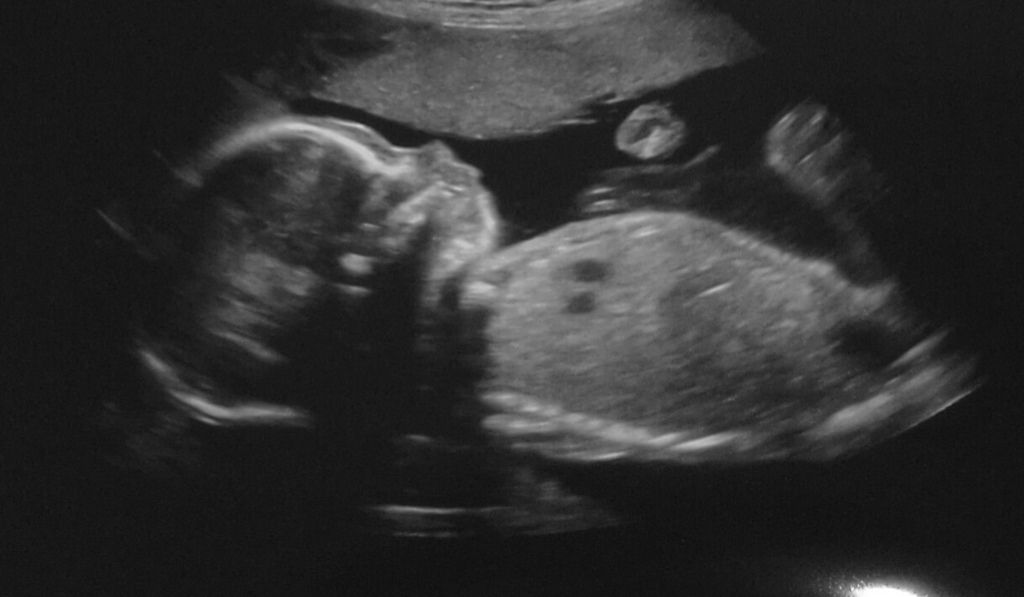

It's a boy!